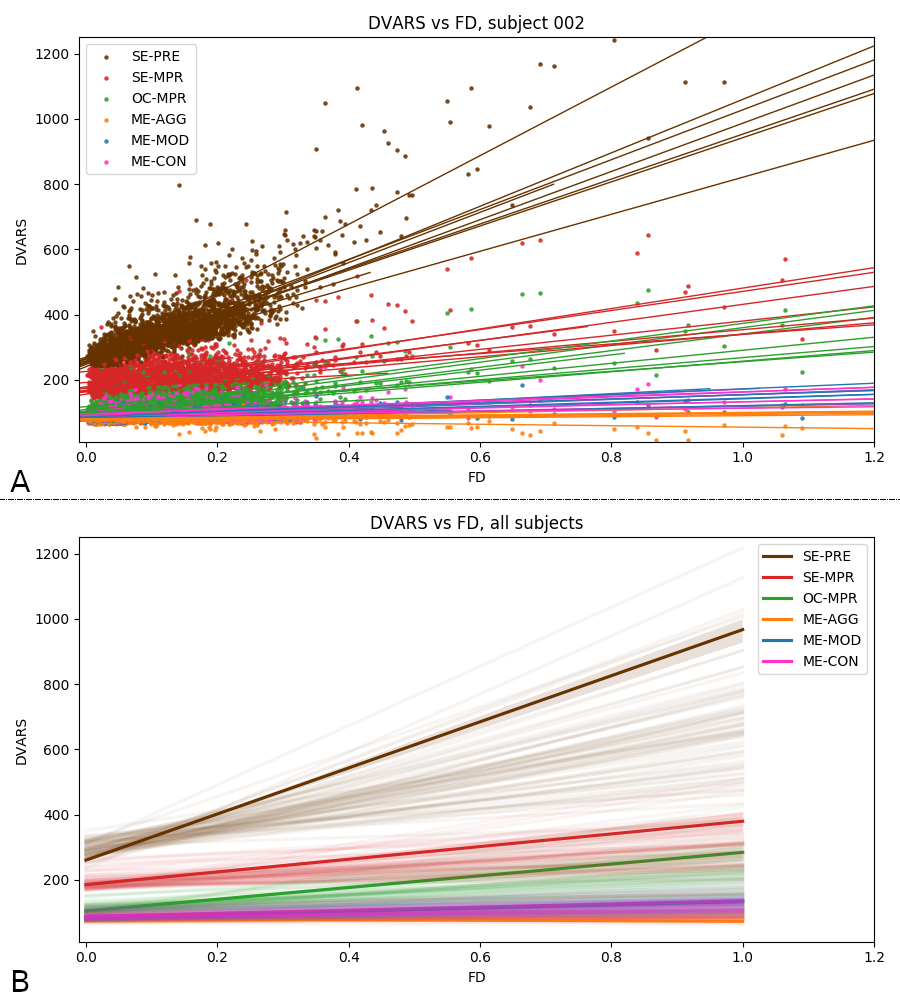

Methods: ME-ICA based denoise

- their effect in terms of making signal (DVARS) independent of motion (FD) [LME]: $$DVARS_t = \sqrt{\lang [I_t(x) - I_{t-1}(x)]^2}$$ $$FD_t=|\Delta d_x|+|\Delta d_y|+|\Delta d_z|+|\Delta \alpha |+|\Delta \beta|+|\Delta \gamma |$$

$$DVARS\sim FD\ast model+(1|subject)+(1|session)$$

Effect of denoising approach is significant for slope (F(5,354)=177.6, p<0.001) and intercept (F(5,354)=225.7, p<0.001) of the linear regression model

DVARS vs FD

Group level, DVARS vs FD

Results: motion removal

Moia et al. 2021 (NeuroImage)